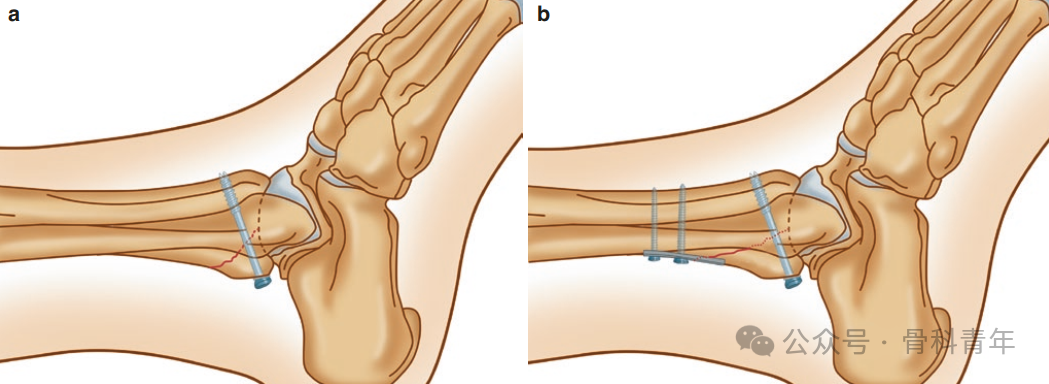

前向后螺钉术中无需翻身,便于手术操作,但无法直视下复位后踝,导针置入时无法精准判断位置; -

后向前螺钉需漂浮体位或仰卧位,操作繁琐;但可在直视下复位,且生物力学研究上,后前螺钉比前后螺钉具有更强的稳定性。

后向前螺钉的置入存在置入下胫腓间隙、激惹踇长屈肌腱及损伤腓肠神经的风险。为避免上述问题,有学者进行了相关标本研究,以明确后踝螺钉置入的安全区。